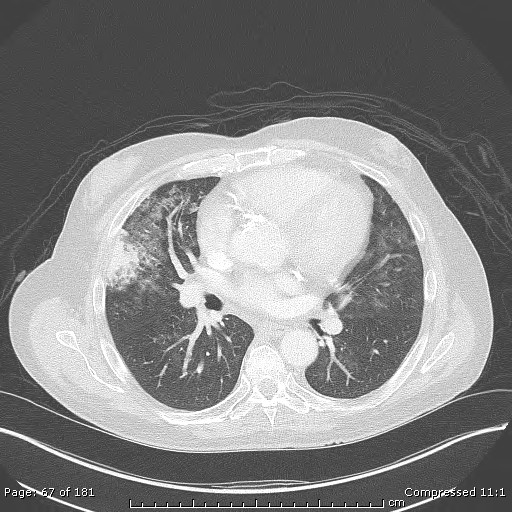

The pathology from the right middle lobe wedge resection is consistent with pulmonary calcinosis. The biopsy shows dystrophic calcifications of the lung interstitium and blood vessels. The term dystrophic refers to calcium deposition in previously injury tissue, as opposed to metastatic calcification, which occurs in non-injured tissue.

Diffuse, nodular calcification can be observed following Varicella pneumonia. Acutely, Varicella pneumonia radiographically appears as scattered, ill-defined pulmonary nodules. These infiltrates typically resolve over time. In some cases, however, calcification occurs three to five years later12. The pattern of calcification is typically punctate or miliary, resembling initial injury patterns. Thus, choice A is incorrect.

Pneumocystis jerovecii pneumonia (PJP, formerly Pneumocystis carinii pneumonia, PCP) is historically regarded as the most common AIDS-defining illness, typically when the CD4+ count falls below 200 cells/mm3. With the routine use of chemoprophylaxis and the emergence of highly active anti-retroviral therapy, the incidence in HIV positive patients has declined14. However, the incidence of PJP in non-HIV immunocompromised patients is increasing, including those who receiving transplants. The radiologic appearance of PJP varies, but common features include ground glass opacities in a perihilar distribution on high resolution computed tomography. Pneumatoceles are common as is septal thickening. Consolidation, lymphadenopathy and pleural effusions are rare. Pathologically, PJP proliferates as a trophozoiote and associates with type I pneumocytes15, which has been demonstrated by electron microscopy. Rarely, calcification of the lung can be seen with PJP and other parasitic infections, however, the clinical history, radiographic appearance, pathologic specimen and chemoproprohylaxis eliminate answer choice C.

Calcification refers specifically to calcium salt deposition within tissues, as opposed to ossification, indicating bone formation. Many tissues have been proven to be highly susceptible to calcification, with the lung more commonly involved than blood vessels, kidneys, stomach and heart16. Pulmonary calcinosis is classified as metastatic, when calcification occurs in previously healthy lung tissue and dystrophic when occurring in previously injured lung. Further subdivision includes benign and malignant causes. Many systemic conditions have been associated with metastatic pulmonary calcinosis, including chronic kidney disease requiring hemodialysis, primary hyperparathyroidism, hypervitaminosis D, the milk-alkali syndrome, and orthotopic liver transplantation. None of the other answer choices listed represents an increased risk for the development of pulmonary calcinosis.

The mechanism(s) by which orthotopic liver transplantation increases the risk of pulmonary calcinosis is not elucidated. Contributing factors include co-existent renal dysfunction, acid-base disturbances, and the administration of exogenous calcium and citrate, primarily through transfusion of blood products intra-operatively12. The importance of blood product administration and the development of calcification was analyzed by Wechsler, et al17. The results showed a statistically significant difference in the number of blood products transfused, specifically fresh frozen plasma and cryoprecipitate, in those patients who underwent orthotopic liver transplantation and developed supra-hepatic circumcaval rings. The development of supra-hepatic circumcaval rings is thought to represent calcification, as occurs with pulmonary calcinosis.